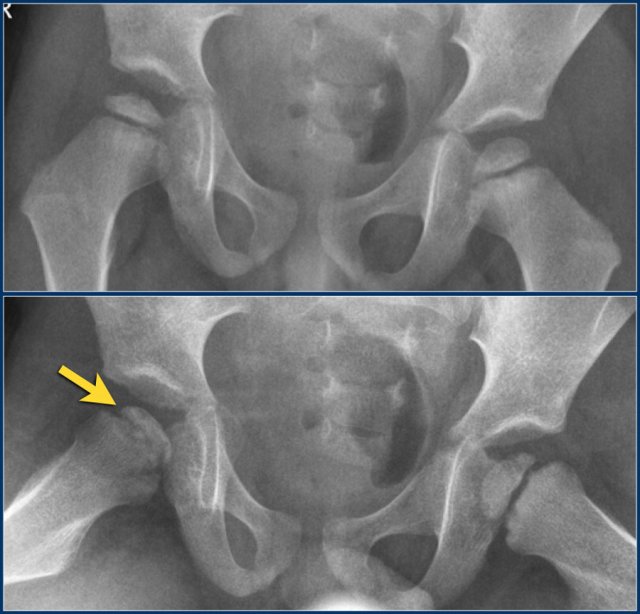

Slipped Capital Femoral Epiphysis (SCFE) or femoral epiphysiolysis is an idiopathic Salter-Harris type I fracture of the proximal femoral epiphysis.

It occurs more commonly in boys and in obese children. The typical age at presentation is between 12-15 years.

SCFE may occur bilaterally in up to one third of cases.

The epiphysis slips posteriorly, and to a lesser extent medially.

It is therefore best appreciated on the frog-leg lateral view.

SCFE is treated with surgical fixation to prevent further slippage.

Avascular necrosis of the femoral epiphysis is a potential complication.